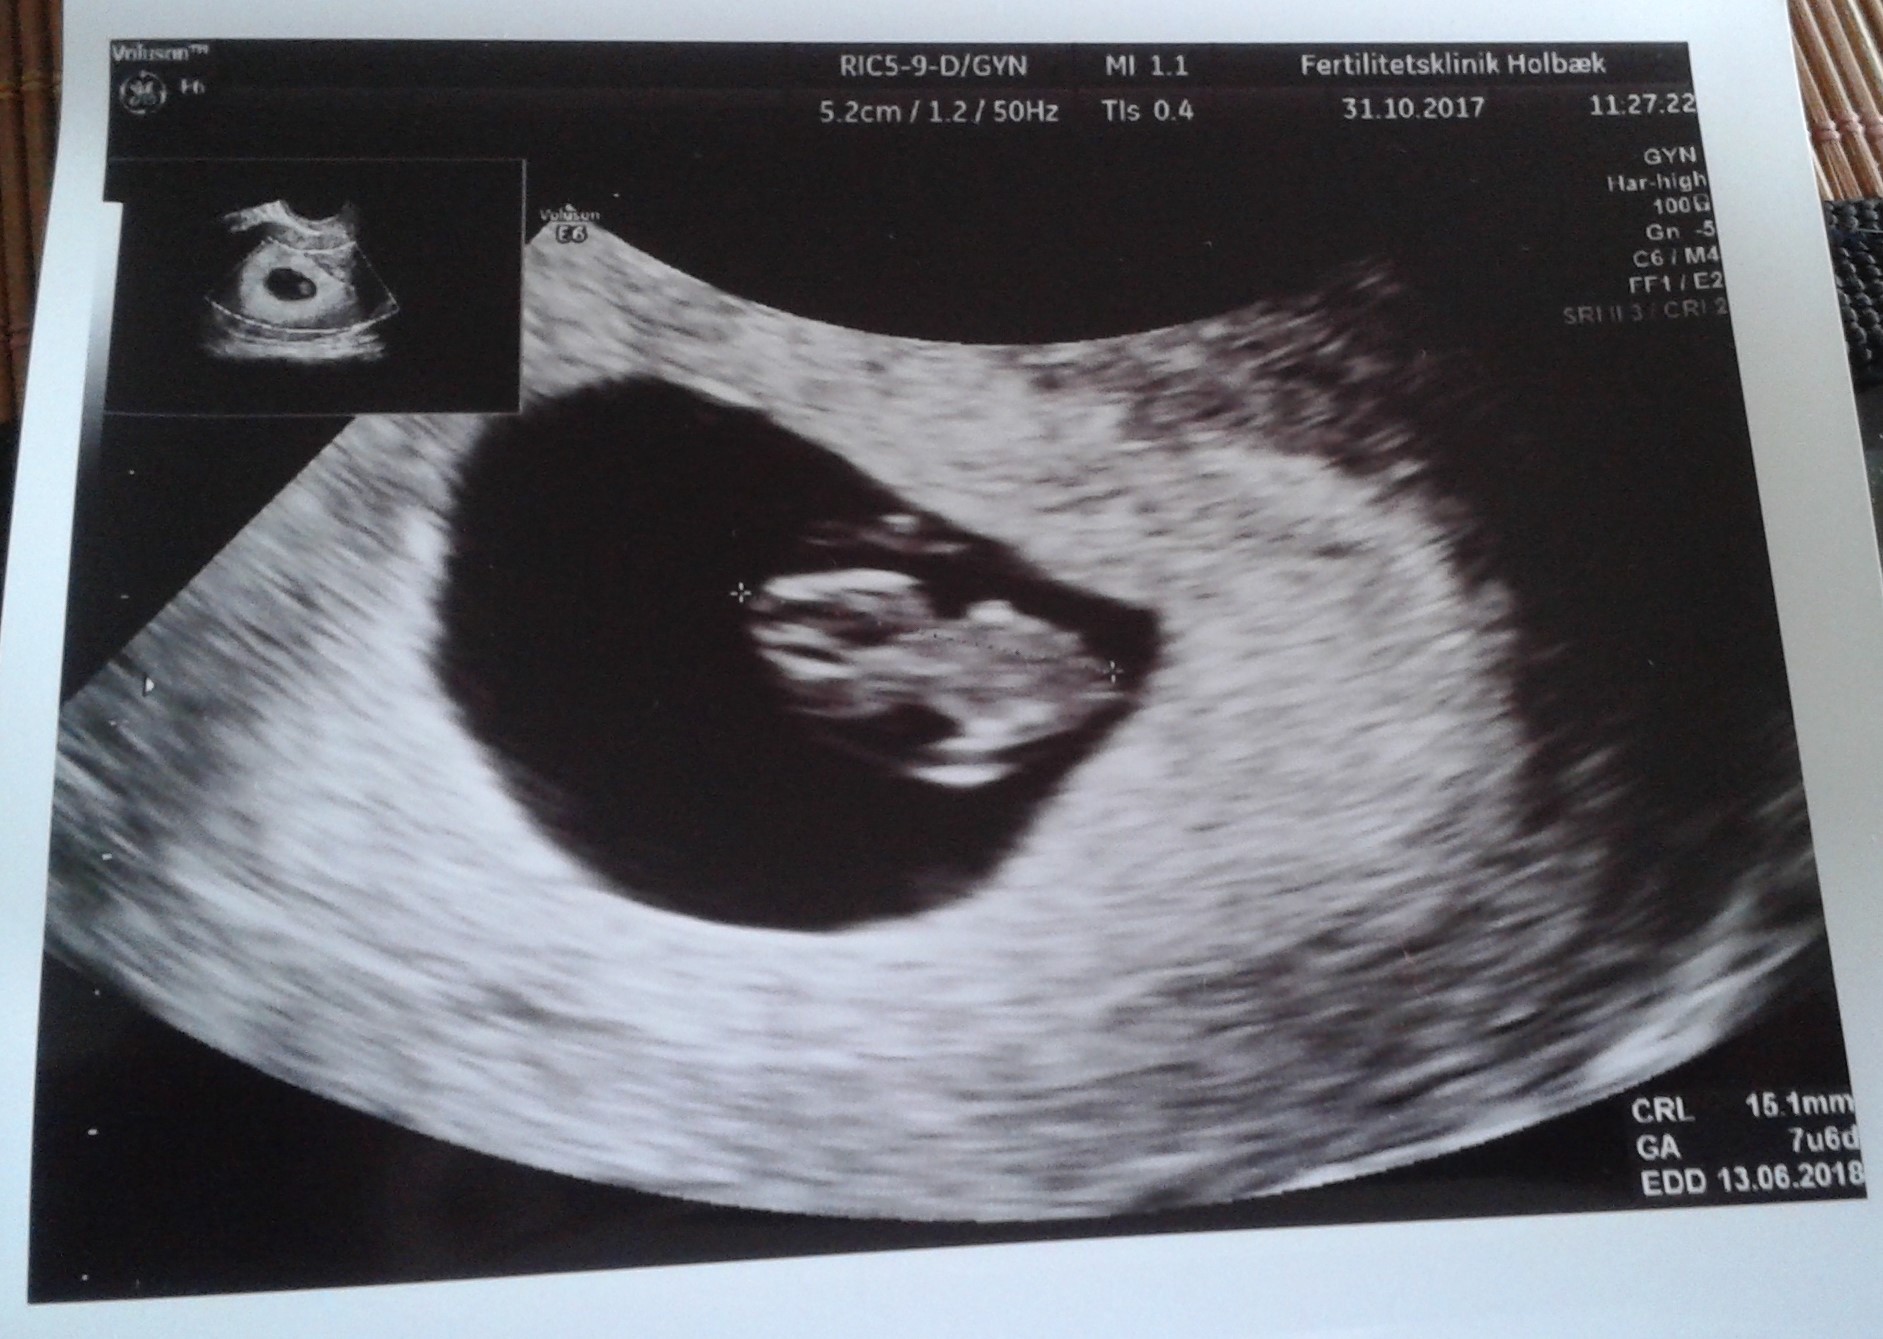

A to moje 15 mm szczęścia. Wszystko jest w porządku. Serduszko bije jak dzwon. Termin wychodzi na 13.06.2018. Tylko mnie dopadło paskudne przeziębienie. Nie mam jak oddychać przez zapchany nos. Ale muszę się przemęczyć. Domowe sposoby poszły w ruch i mam nadzieję, że pomogą. Zobacz załącznik 827730